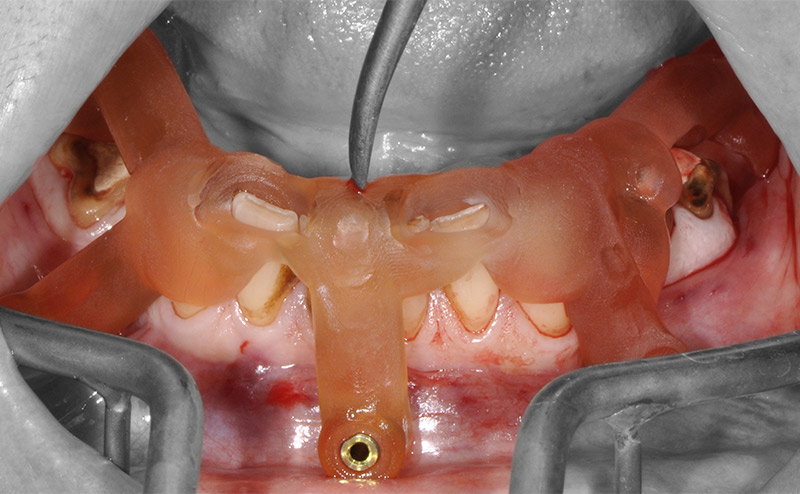

Fig. 51 : les dents sont extraites sans lambeau par fractionnement puis le guide de résection osseuse est inséré et claveté dans les emplacements précédemment forés.

Fig. 52 : le guide de forage et de mise en place des implants est empilé sur le guide de résection osseuse.